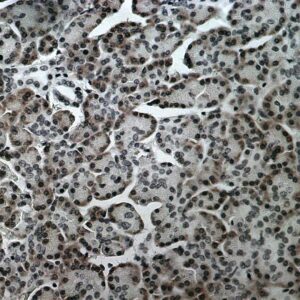

BioGenex has pioneered the development of miRNA research and diagnostics tools with leading-edge products. Currently, we offer over 240 ready-to-use (RTU) Super Sensitive™ Nucleic Acid (SSNA) miRNA ISH probes for accurate and early tumor diagnosis. These probes are sensitive enough to detect low-abundant miRNA(s) that are often required to identify biomarkers. They have a high melting temperature enabling stringent washes to remove non-specific binding. BioGenex miRNA probes are dual-end labeled with an anti-fluorophore to amplify the signal and yield clean and intense staining.